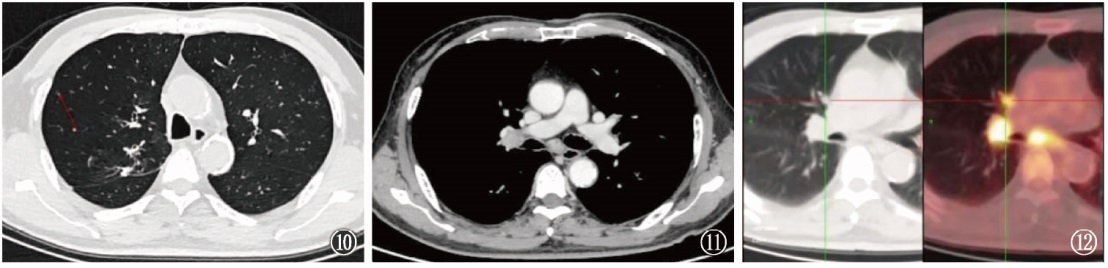

图4~9肺结核与肺癌共病的影像学表现。 图4~6为同一患者,既往肺结核病史;图4可见患者右肺上叶后端残留支气管扩张;图5显示患者7个月后支气管扩张区呈黏液嵌塞征表现,周围散在结节影;图6显示患者13个月后支气管扩张的管腔内软组织病变生长呈典型支气管铸型征表现;行支气管镜组织活检,病理诊断为鳞癌;同时,气道分泌物抗酸杆菌涂片阳性,提示结核病复发。图7~9为同一患者,诊断为左上叶活动性肺结核,涂阳,初治。图7为患者治疗前,右肺中间段支气管未见明显异常;图8为患者经抗结核治疗后病变逐渐吸收,但右肺中间段支气管略见狭窄,未采取措施;图9为患者抗结核治疗5个月后复查CT,可见肺结核病变显著吸收,中间段支气管管壁狭窄直至闭塞,不符合结核病转归病程,呈“矛盾现象”;支气管镜活检病理诊断为鳞癌。